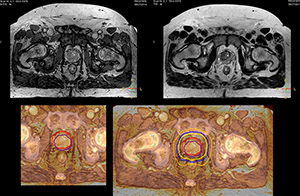

Beaumont Health System brought MRI into its radiation therapy routine practice by implementing the comprehensive Ingenia 3.0T MR-RT Oncology Configuration.

“We currently use MR-RT mainly in the abdomen and pelvis region: prostate, colorectal, pancreatic, cervical, and liver. Also in the brain, we are starting to use it,” says Dr. Yan.

Impressive clinical benefits for prostate

“The biggest problem for CT-based planning, especially in prostate, is you can’t see the cancer very well,” says Dr. Stevens. “On CT it can be quite challenging to see the edge of the prostate especially at the apex. When the edge of the prostate can’t be delineated well on CT, radiation oncologists will increase their margins a little bit so they don’t miss it, but that can also increase toxicity.”

“Using MR, the prostate is well delineated. We quickly see the edges of cancerous tumors like in prostate cancer, and as normal structures can be defined, we can optimize the treatment plan to protect these organs and their normal function. This can potentially improve the outcome. And it improves workflow as well. We can contour more quickly, confident that the tumor is going to be in the field.”

“The Ingenia 3.0T MR scanner provides high resolution allowing us to make scans fast for the patients. It also gives the potential to include methods like MR spectroscopy and diffusion weighted Imaging, which we’re in the process of doing right now,” Dr. Stevens adds.